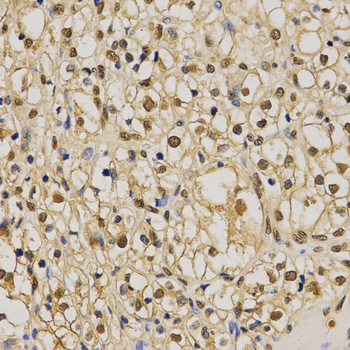

Immunohistochemistry of paraffin-embedded human kidney cancer tissue using H3K79me2 antibody at dilution of 1:200 (x400 lens).